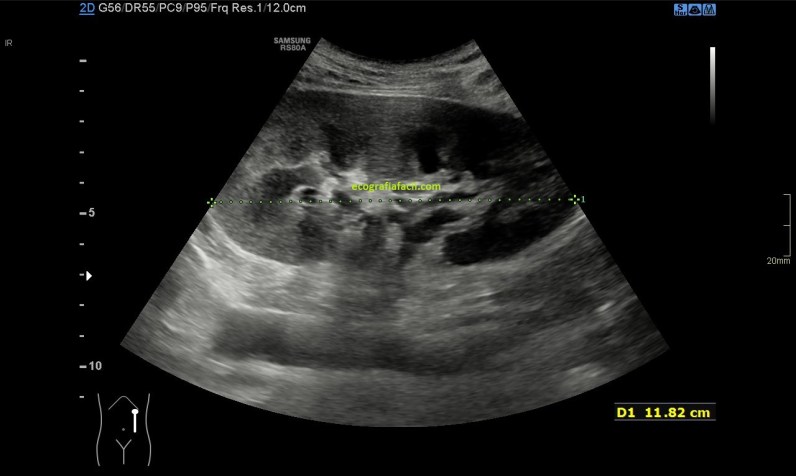

Me dirigí a la fosa renal izquierda, exploré el riñón locoregional, imagen 3, de tamaño normal, en ocasiones los riñones aumentan su tamaño en el contexto de la ausencia del otro riñón, ya que cuando tenemos ausencia de uno de los dos riñones en determinadas circunstancias, el contralateral compensa la función del que no funciona bien, y lo hace hipertrofiándose.